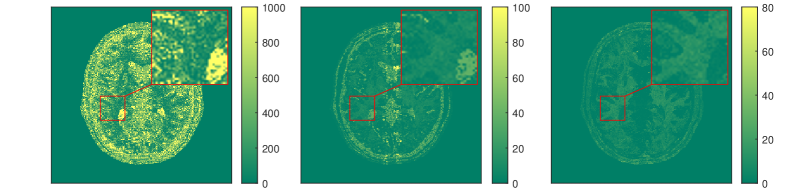

Very large values of regularization parameters typically result in over-regularization leading to over-smoothed reconstructions. While this might benefit the reconstruction of large homogeneous areas in images (where ) it can also result in cartoon-like reconstructions with a significant loss of details. On the other hand, very small values of regularization parameters generally preserve details but may also yield reconstructions with noticeable noise and artifacts due to the underlying ill-posedness; compare Figure 1 for a representative example in (qualitative) MRI reconstruction. This suggests a local adaptation of the regularization strength which can be achieved by a spatially varying regularization parameter / weight. Here the parameter (and also in TGV) is spatially varying (pixel-dependent) rather than a scalar only. Thus, one has , and similarly for . Then the corresponding regularization functionals, i.e., weighted TV and TGV, are defined in their discrete version respectively as follows:

where denotes all relevant regularization parameters, such as for instance in (2.5) or in (2.6). Furthermore, denotes an upper level objective which is to be minimized over both the image and under the constraint that is the solution of the variational problem with regularization parameter . Borrowing terminology from mathematical game theory, one may consider the “leader” and the “follower”, that accepts any choice of issued by the leader and reacts optimally by minimizing the objective in the constraints of (2.7). Consequently, as in the above primal-dual equilibrium setting has to implement criteria for measuring the quality of . For instance, may equal the distance of to the ground truth , i.e. . In practice, this approach typically involves a training set of true data in the spirit of supervised learning [31, 54] which, however, makes the approach susceptible to overfitting [55]. This can be remedied by developing ground-truth-free upper level objectives like the one introduced in [96, 97] for TV, which is inspired by a dual version of the localized residual estimators of [61]. Later this approach was also used for TGV and general convex regularizers [102, 147]. As in [61], there are statistics-based objectives aiming to enforce a localized version of the residuals that allows the computation of spatially varying regularization parameters without using any ground truths. In Figure 2 we depict a TGV-based qualitative MRI reconstruction where the regularization parameter of TGV is spatially varying and computed by the ground-truth-free bilevel approach in [102, 177].